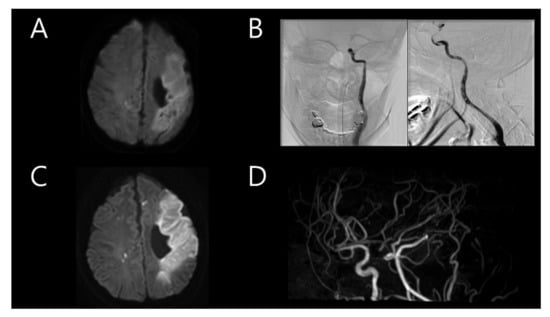

Five and a half years after the first stroke, the patient was re-admitted for sudden dysarthria. A neurological examination revealed alert mental status, mild dysarthria, left facial palsy, and left hemiparesis (MRC grade 4/4). Brain CT angiography indicated recent severe stenosis in the M1 portion of the right MCA, with previous occlusion in the left MCA (Figure 2A). Intravenous tPA was administered, with an onset-to-door time of 2 h and 20 min. Moreover, TFCA was conducted to examine the right MCA stenosis, which was distinct from the previous event, even though the patient did not display severe cortical symptoms. During right ICA angiography, intramural hematoma and intimal flap were detected in the M1 portion of the right MCA, indicating arterial dissection (Figure 2B). A brain MRI and CT performed after TFCA revealed multifocal acute infarction in the right MCA territory (Figure 2C,D). TTE did not reveal any significant changes compared to the previous examination. The results of screening tests for autoimmune diseases and vasculitis (antiphospholipid antibodies, lupus coagulant, and antinuclear antibody screening and all subtypes that could possibly be tested) to further evaluate the etiology of stroke in this young patient were all negative. The chromosome analysis result was also normal. Therefore, medication and rehabilitation therapies were administered.

Figure 2. (A) Brain computed tomography angiography conducted on the second event which occurred after 5.5 years, showing recently formed severe stenosis in the M1 portion of the right middle cerebral artery (MCA), with left MCA occlusion present from the past stroke event. (B) Immediate cerebral angiography showing intramural hematoma and intimal flap in the M1 portion (arrow) of the right MCA. (C,D) Follow-up brain magnetic resonance imaging showing a multifocal acute infarction in the right MCA territory.